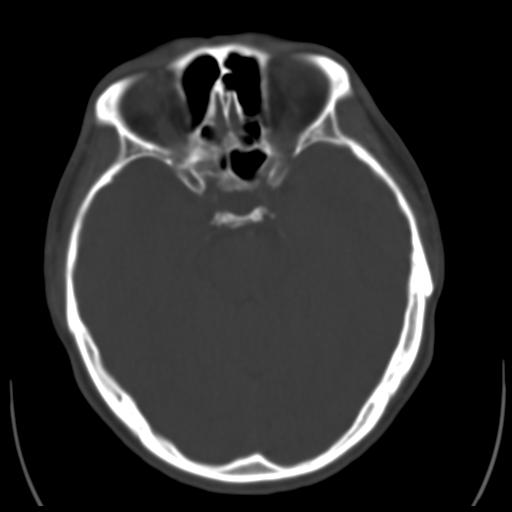

35m 鼻子时不时流血,头及右侧面部痛,颈部淋巴结未见明显大

软组织窗

这个东西大家仔细看看呀

考虑鼻咽癌侵犯颅底并突入右侧鼻腔;双侧中耳乳突炎。

建议:必要时行鼻咽镜检查(活检)进一步明确诊断。

蝶窦,后组筛窦及鼻咽部团块状软组织影,骨壁破坏,病变较广泛。考虑恶性肉芽肿。建议活检。

颅底骨质明显破坏 支持鼻咽癌 但病灶的边缘毛糙 不能除外炎性

蝶窦,后组筛窦及鼻咽部团块状软组织影,骨壁破坏,病变较广泛。考虑炎性肉芽肿性病变可能。建议活检。